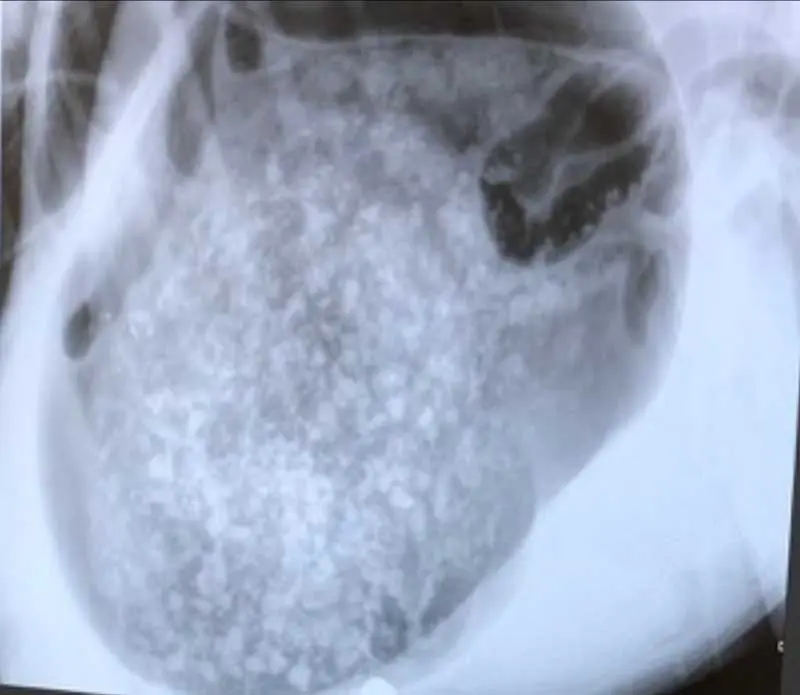

A variety of diseases can affect the stomach, from acute and chronic inflammation to ulcers, infections, foreign bodies, gastric dilation volvulus (GDV; Figure 1) and neoplasia (Jones, 2024). Reducing stomach acidity using proton-pump inhibitors and gastroprotectants to protect the ulcer are the key nursing considerations while ensuring the patient is nutritionally supported and providing additional aid such as fluid therapy, assisted nutrition such as feeding tubes and anti-emetics where required (Jones, 2024).

GDV is an acute life-threatening condition that normally affects our deep-chested breeds such as great Danes, German shepherds, Dobermanns and even dachshunds. The stomach twists, which causes gas to accumulate and become trapped in the stomach, causing the dilation, and the stomach then decreases the blood supply to the heart, leading to shock, hypotension and hypovolaemia. This decreased blood supply can eventually lead to sepsis, arrythmias and disseminated intravascular coagulation (DIC) and death if not treated (Jones, 2024).